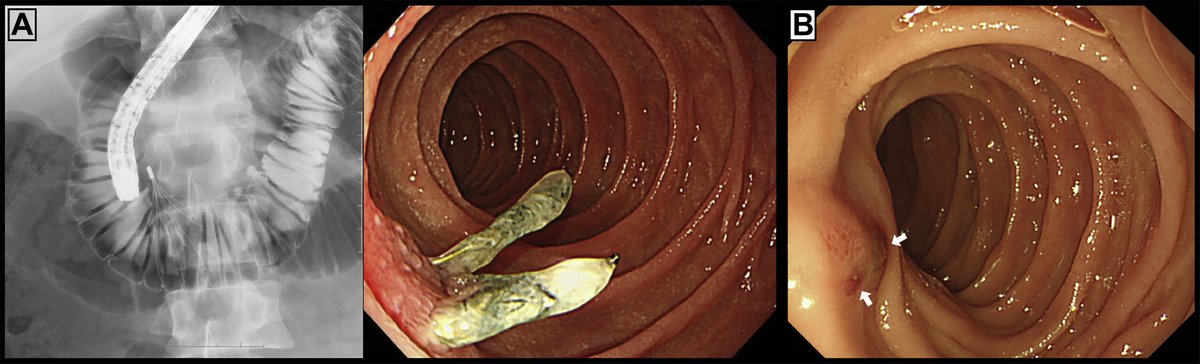

Young patient (30’s) w/ small PE & #symptomatic #subacute #iliocaval #DVT extending above #IVCFilter. #Inari #ClotTriever #Thrombectomy

3 month old #IVCfilter with iliocaval occlusion, bilateral leg edema. Crossed both CIV occlusion from below, forceps #Filterout with 18Fr sheath then 18mm wallstent iliocaval reconstruction. #WeCanRecan